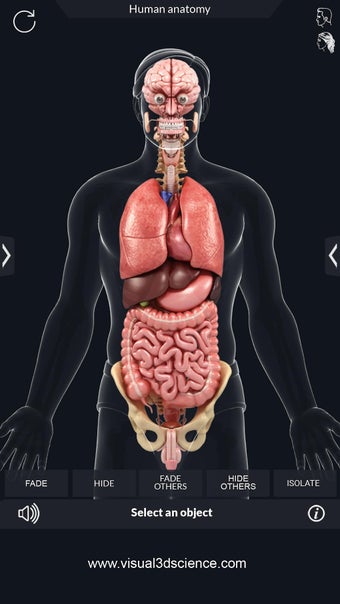

Met deze applicatie kun je 360° draaien rond een zeer realistisch 3D-model van het menselijk lichaam. Je kunt in- en uitzoomen op elk deel om er beter naar te kijken.

De camera kan worden verplaatst om een ander beeld van elk deel te krijgen.

Je kunt alle informatie over de organen krijgen, inclusief hun locatie, hun functie en hoe ze eruitzien.